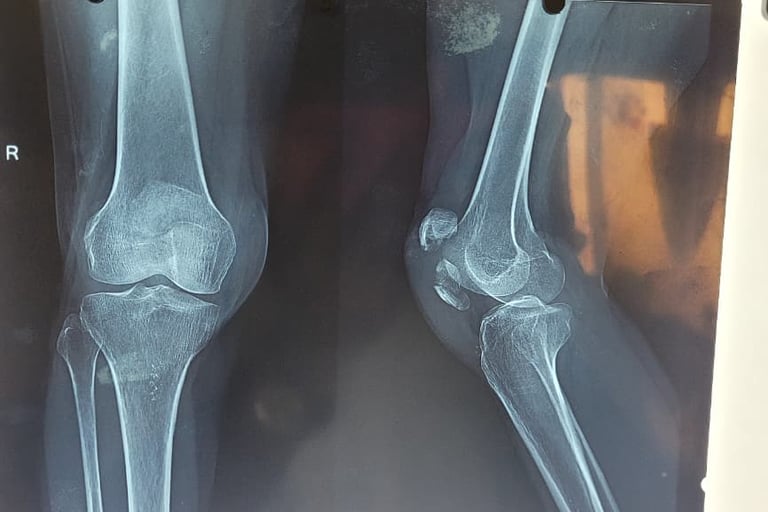

Patella Fracture – Understanding the Injury and Its Treatment

A patella fracture (kneecap fracture) is a common knee injury that usually occurs due to a direct fall on the knee, sports injury, or road traffic accident. The patella plays an important role in the knee extensor mechanism, helping the quadriceps muscle straighten the leg for normal walking and movement.

In some cases, the fracture becomes displaced, meaning the broken bone fragments move apart. A two-part displaced patella fracture disrupts the normal knee function, making it difficult or impossible for the patient to straighten the leg or walk properly.

Such fractures usually require surgical fixation using K-wire and Tension Band Wiring (TBW). This procedure helps to realign the broken fragments, stabilize the bone, and restore the knee’s extensor mechanism, allowing proper healing and recovery.